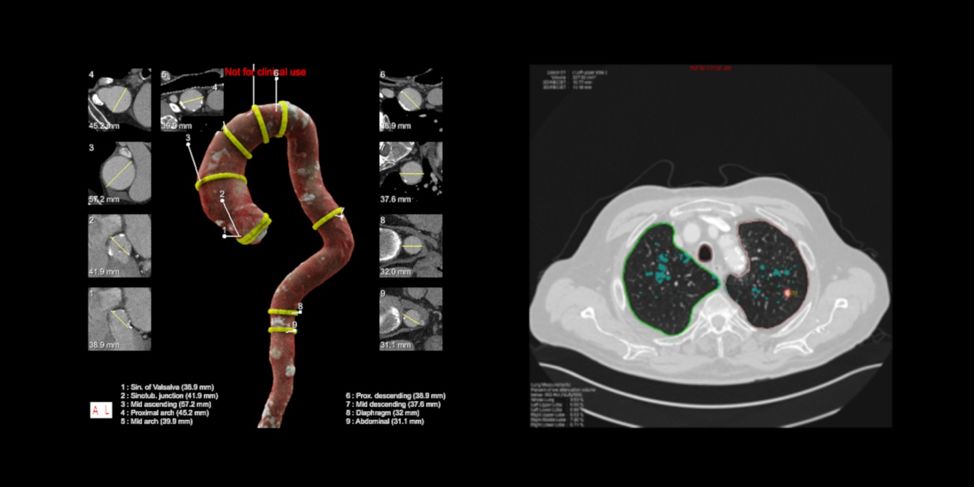

西门子的AI-Rad系统针对胸部CT影像,提供多方面的测量、定位和自动报告生成功能。比如,借助影像分割技术,找出胸部CT影像中大动脉的像素级定位,实现对动脉直径等多方面的自动化测量。该系统还利用目标检测技术,对体内器官的各项异常进行定位和初步诊断。

在早期肺癌筛查中,AI可以准确地识别出肺部小结节的位置所在,并对结节进行初步分析,帮助医生尽早做出诊断,大大提升早期肺癌的发现率。根据美国国家肺部筛查试点研究组的研究数据,借助肺结节早期筛查,逾20%的肺癌罹难者将有机会幸免于难。

(AI-Rad系统,图片来自西门子)